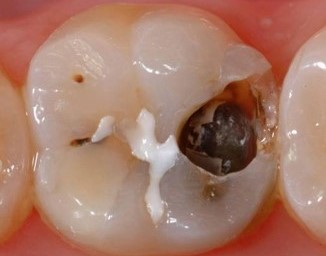

How does SDR Plus provide reliable adhesion and a tight seal to protect the proximal box? Here is how this bulk fill composite allows dental practitioners to place gap-free restorations:

SDR® Plus is optimized for bulk filling posterior cavities that are challenging to access during a dental treatment. Unlike conventional filling materials, it is flowable and can be placed in up to 4 mm increments. This allows dental practitioners to fill a large portion of the posterior cavity in just one step with a flowable material that adapts itself to the cavity walls without further instrumentation. The unique chemistry of SDR® Plus also minimizes shrinkage stress that otherwise could lead to gap formation during light curing.

Using SDR® Plus has a number of advantages, including a reduced risk of postoperative sensitivity and enhanced marginal integrity, which is an important factor in the prevention of secondary caries. It also makes the creation of a uniform, void-free restoration easier thanks to the material's self-leveling qualities, and its high radiopacity simplifies monitoring of the restoration over time.